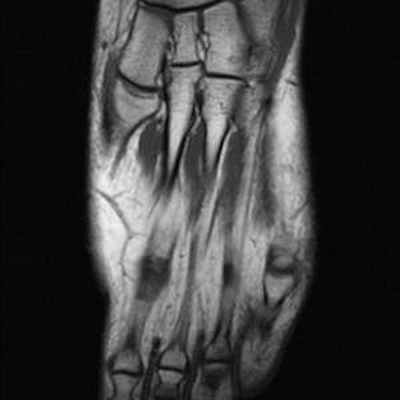

Головка 2-ой плюсневой кости выглядит сплюснутой и расширенной с правой стороны в связи с болезнью Фрейберга.

Отсутствие внутрикостной отёчной инфильтрации по краям суставной щели плюснефалангового сустава. Напротив, следует отметить наличие внутрисуставного выпота.

Для диагностики заболевания обычно бывает достаточно обычной рентгенографии, но иногда доктор может назначить МРТ либо исследование радиоизотопным методом.

Сначала будет сделан рентгеновский снимок, но его недостаток в том, что он может не показать Фрейберга на ранней стадии. Один МРТ обследование - самый полезный инструмент для раннего обнаружения Фрайберга. Исследование 3D CT может дать хорошее представление о том, насколько обширны повреждения от некроза.

МРТ также может использоваться для оценки состояния, и помочь в раннем выявлении болезни Фрейберга, когда рентгенограммы не имеют изменений. Другие исследования, такие как лабораторные исследования, также могут быть рекомендованы для исключения других состояний, вызывающих подобные симптомы.